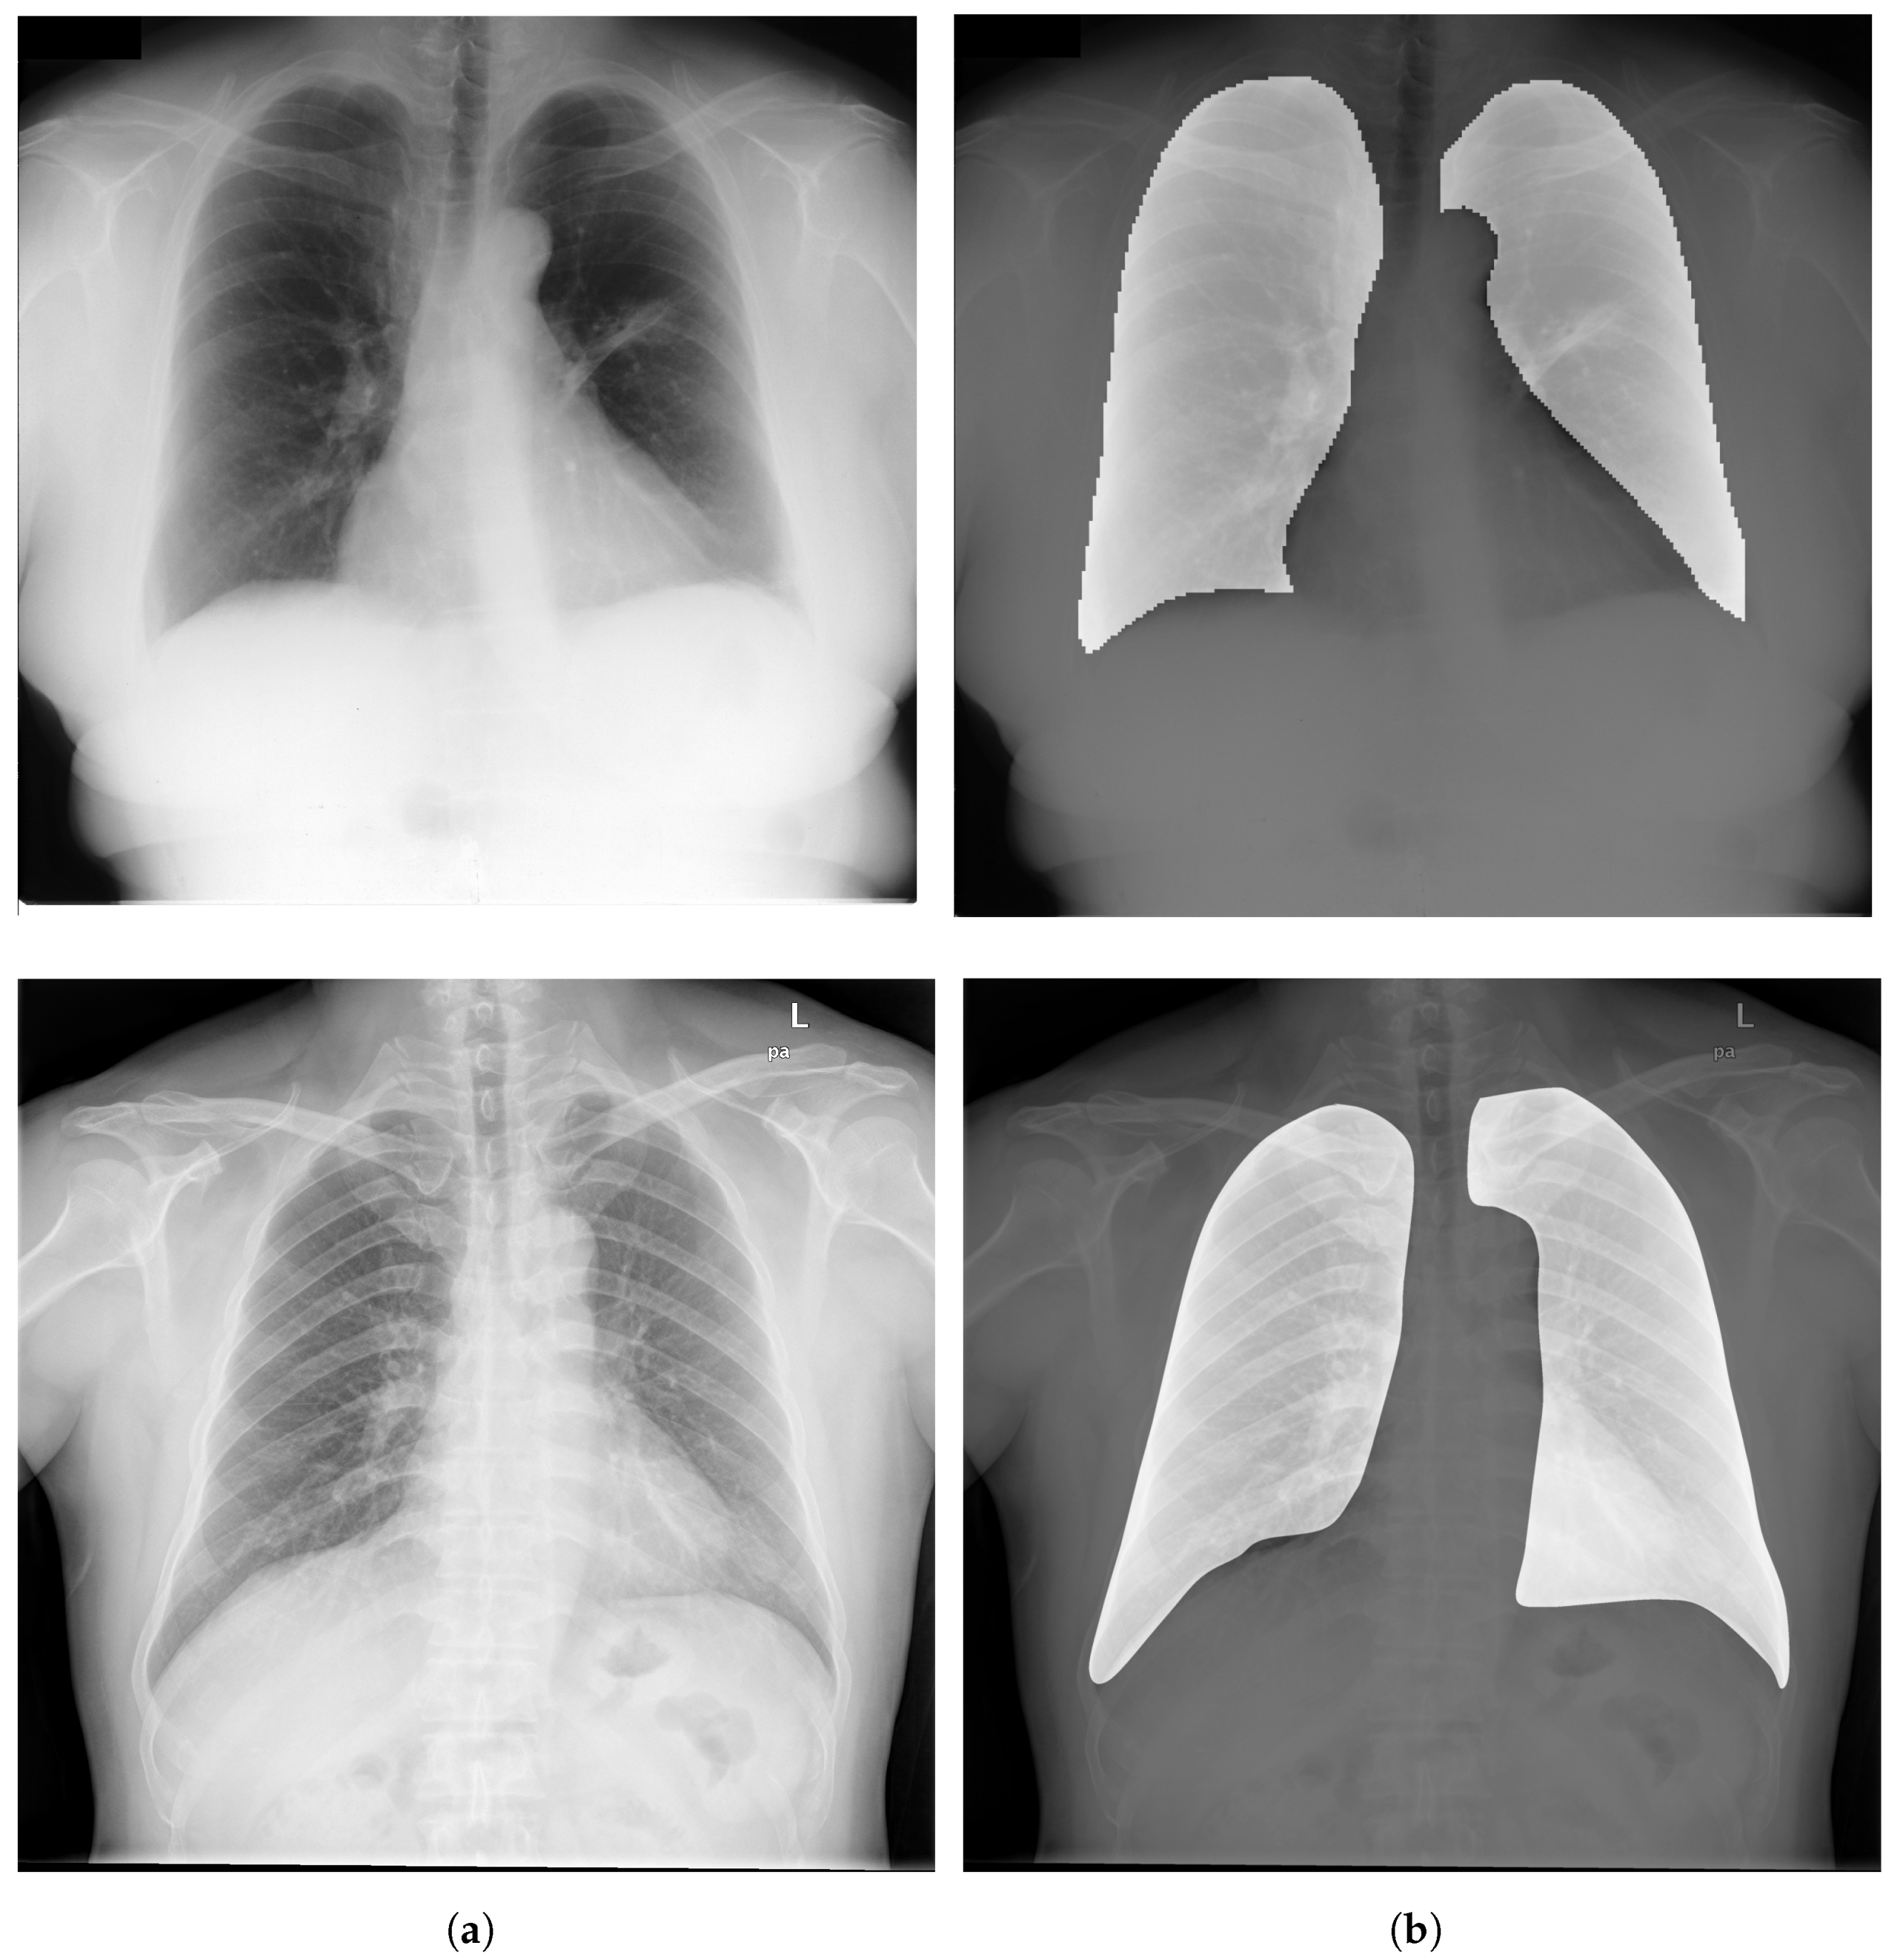

3.3. Segmentation

Image Segmentation has a critical rule in image preprocessing techniques. It is usually necessary to divide a visual image into fragments. For CXR images, this technique allows segmenting the thoracic image into areas in order to extract the ROI. Figure 6 depicts examples of ROIs overlaid on CXR images.

Figure 6.

(a) Examples of CXR images from CheXpert dataset [44]; (b) Samples of ROIs overlaid on CXR images.

3.4. Bone Suppression

Bone suppression is a technique that can be applied on CXR images. It is an important step in the process of lung segmentation and extraction of features from thoracic images. Bone suppression technique is based on removing the bones from the CXR images, as depicted in Figure 7. It helps to increase the visibility of obscure zones and to prevent the overlap of signs of diseases with ribs and clavicles. An overview of bone suppression techniques applied to CXR images is presented in Table 6.

Figure 7.

(a) CXR image from CheXpert dataset [44] before bone suppression; (b) CXR image after bone suppression.